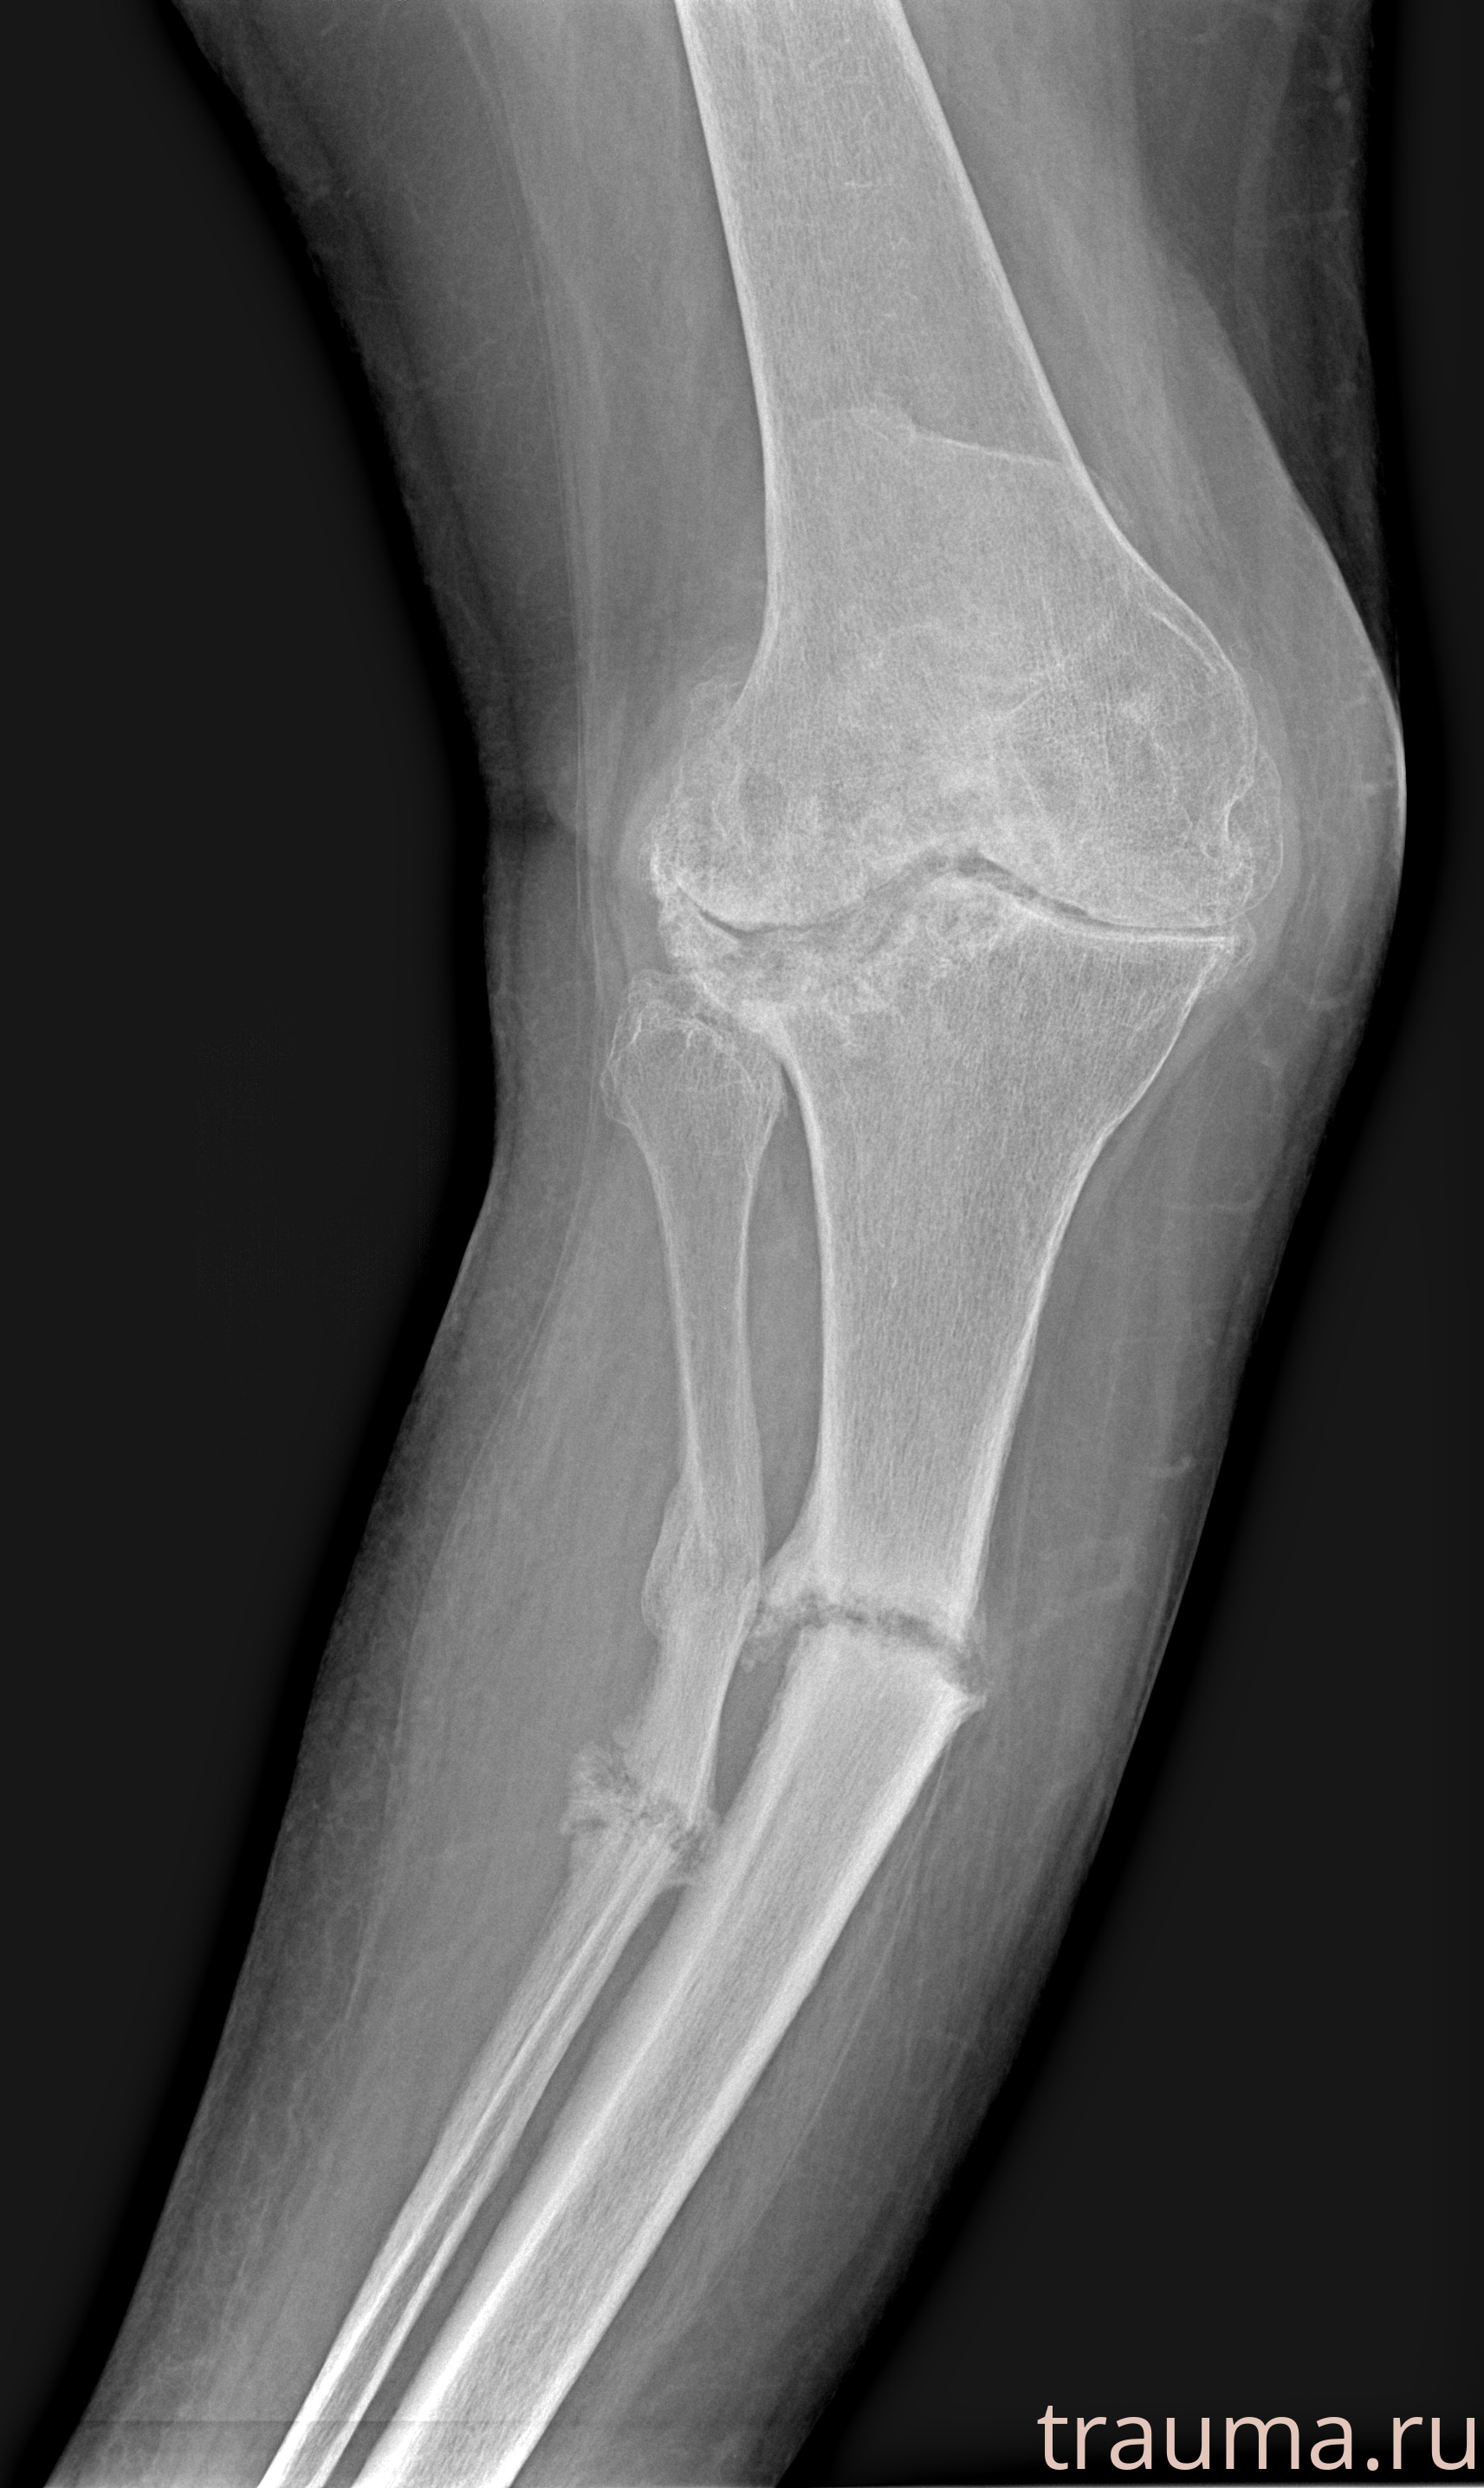

Рентгенограммы

Рентген на дому: по вашему адресу приезжает врач-рентгенолог, травматолог-ортопед с мобильным рентгеновским аппаратом, проводит диагностику травмы или заболевания, делает необходимые рентгенограммы, дает рекомендации по дальнейшему лечению. Получить качественные снимки в домашних условиях возможно благодаря уникальной методике, разработанной МосРентген Центром для института  Склифосовского